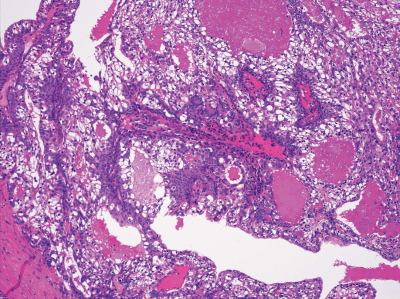

43 歳の女性。口蓋部の腫脹を主訴として来院した。3年前に気付き、その後徐々に大きくなったという。腫脹は弾性硬である。初診時の口腔内写真、MRI T2 強調像及び生検時の H-E染色病理組織像を別に示す。

診断名はどれか。1つ選べ。